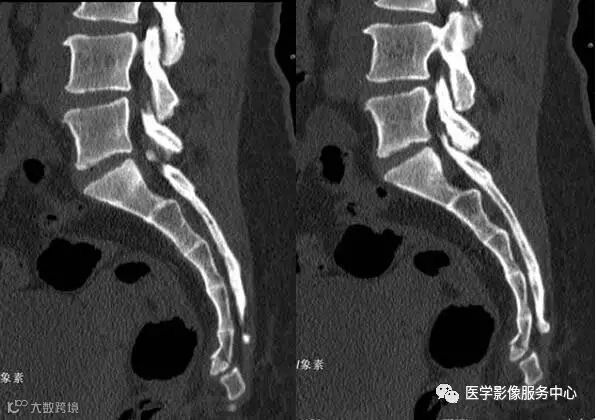

附病例(X线+CT)

病人女性,外伤后骶尾部疼痛,dr片示骶尾关节对应关系差,骶5椎体欠规则。ct重建示骶5椎体粉碎性骨折!

X线

CT